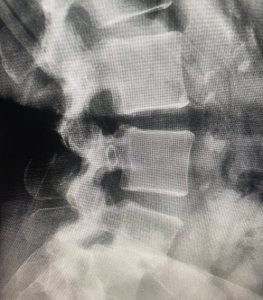

At Texas NeuroSpine Surgery, our goal is to always find the least invasive approaches for the best surgical outcome. However, some cases require more extensive approaches, as in this case of an L4-5 deformity in a patient with rheumatoid arthritis and years of debilitating low back pain. A “front-back” or “anterior-posterior” surgery was needed to correct her deformity and stabilize her spine.

A few weeks after surgery, the patient was off pain medication and resuming work and normal activities. Although not every patient recovers as quickly, this type of extensive surgery offers a solution to many patients who have failed less invasive treatment.